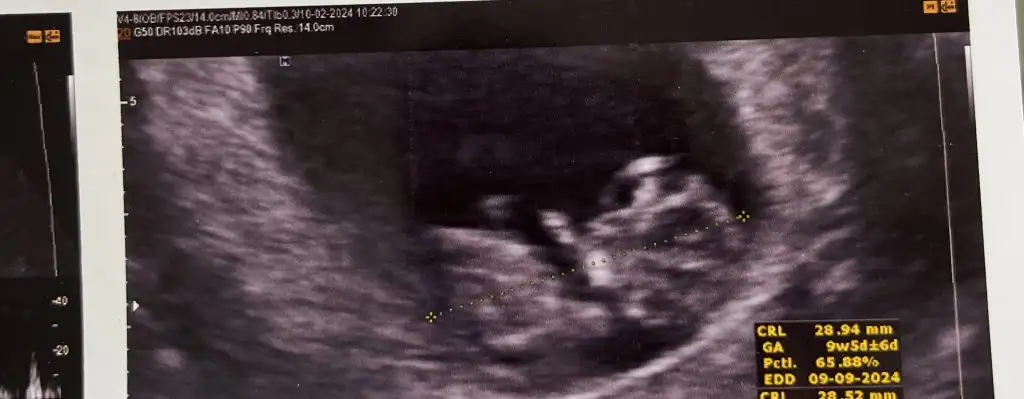

Hay hadi o gün gelsin belki sana söyler doktor cinsiyeti bana demedi göstermedi ya bir ay sonra gel dediİnşallah biz de gittiğimizde 10+5 olacağız. Merakla bekliyorum ben de miniği.Maşallah senin minişe de Allah sağlıkla kucaklarımıza almak nasip etsin